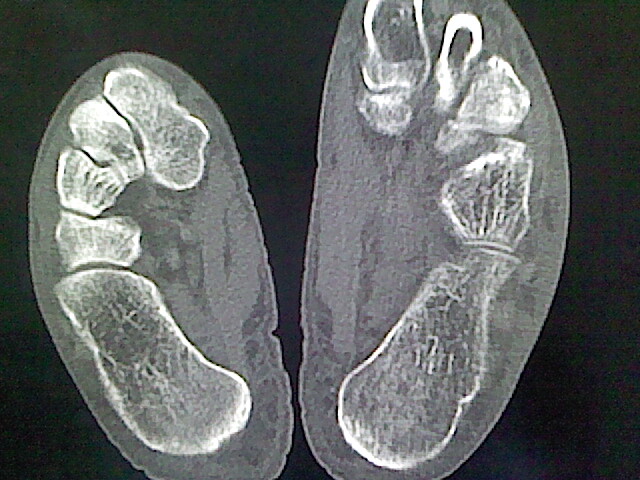

标题: CT16814:男,76岁,左小腿疼痛,不能站立 大家给看看 [打印本页]

男,76岁,左小腿疼痛,不能站立

本例骨质改变主要表现为滑膜或韧带区的骨侵蚀融解(胫腓联合区骨质破坏无硬化边),距骨后部骨质破坏区有硬化边及死骨样改变.所以,本例考虑关节结核可能性大,绒毛膜结节性滑膜炎多发于中年,且极少见于膝髋以外的关节,骨质硬坏也以压陷吸收为主,有明显的硬化边,骨膜增生呈结节状(可以mr鉴别),所以本例暂除外.

另不除外可引起相似表现的其他炎症如布氏杆菌性关节炎等